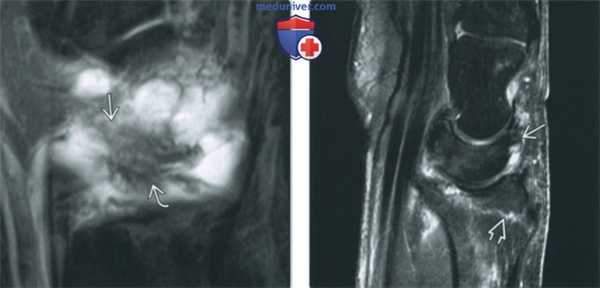

(Слева) МР-артрография в режиме Т1ВИ FS, коронарный срез, этот же пациент: визуализируются поврежденные волокна тыльной межзапястной и лучетрехгран-нойВ связок.

(Справа) МР-артрография в режиме PD FS, сагиттальный срез, пациент, перенесший перелом дистального отдела лучевой костив: визуализируется отрыв небольшого костного фрагмента за счет тяги луче-полулунной связки.